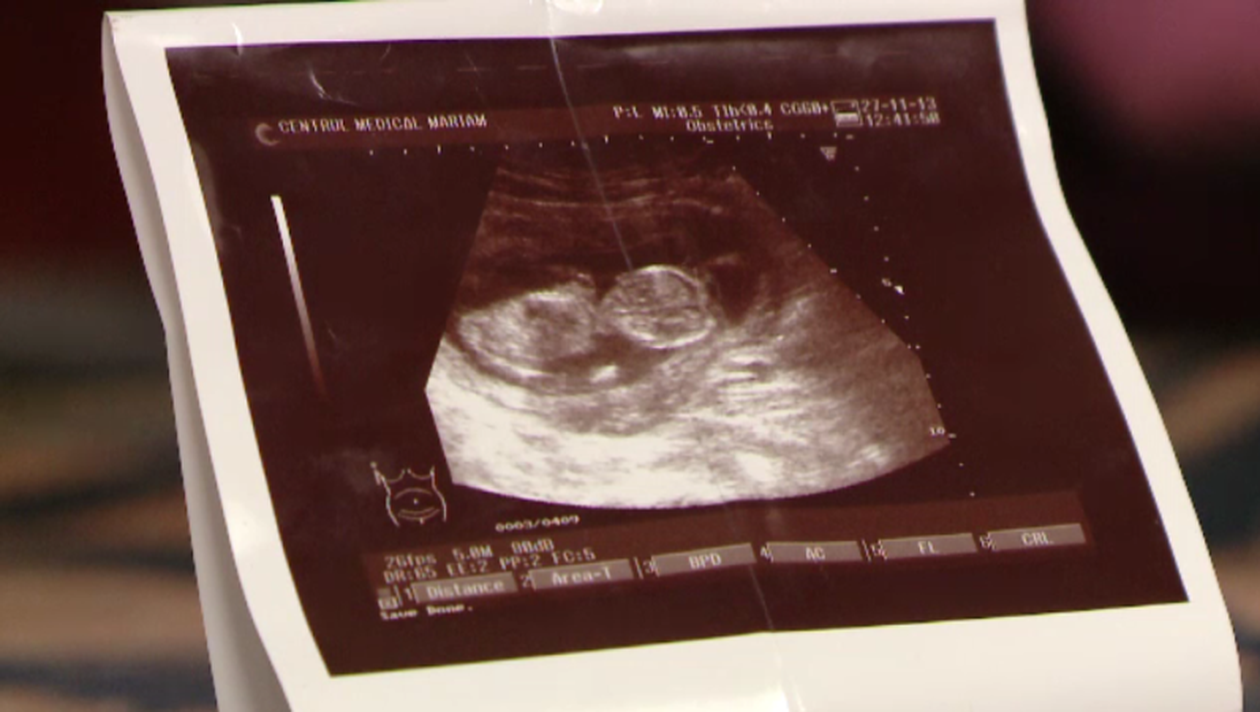

Adelina Socaciu, o graviduţă din Timişoara, a mers la medic pentru a-şi face chiuretaj. Câteva zile mai târziu a descoperit că era tot însărcinată, iar explicaţia e una copleşitoare.

“Doamna doctor spune ca mi-a facut chiuretajul, dar se poate sa fi avut gemeni si sa fi scos doar un fat iar, al doilea sa fi ramas”, povesteste Adelina Socaciu.

Femeia este convinsă că ar fi avut o sarcină dublă, deşi ecografia făcută înainte de intervenţie nu arăta o sarcină dublă. Medicul s-a oferit să îşi repare greşeala şi să termine intervenţia gratuit. Graviduţa însă a refuzat şi a decis să păstreze bebeluşul, urmand sa i se faca analize suplimentare pentru a vedea daca sanatatea micutului a fost sau nu afectata de tratamentul cu antibiotice.